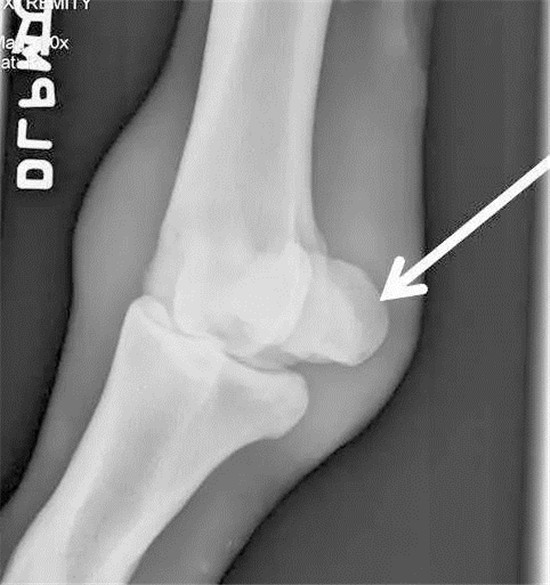

▲“巨鹰拍翼”近端籽骨骨折X光下摄片,图片来源Racing UK。

▲X光拍摄马匹球节部位

▲正常近端籽骨侧位图

▲“巨鹰拍翼”近端籽骨骨折斜位图,可发现近端籽骨明显裂开。图片来源Racing UK。